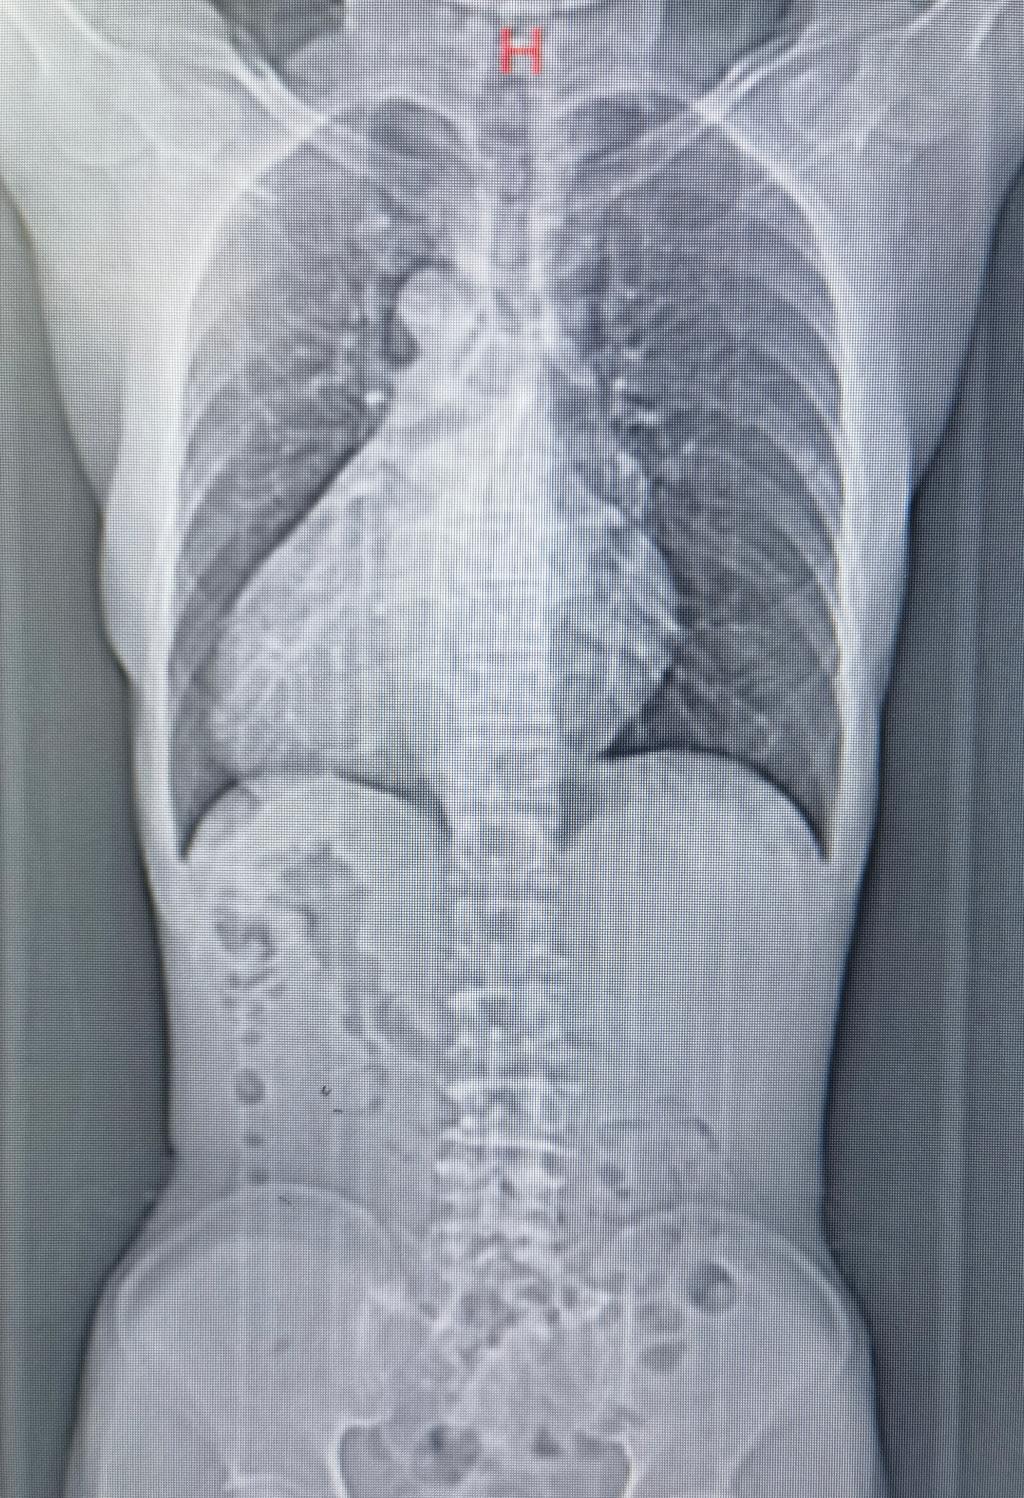

2023年6月25日,井冈山大学附属医院心胸大血管外科收治了一位57岁的男性患者金先生,金先生一个月前因“心慌、闷气”来我院就诊,做心脏彩超检查时发现自己的二尖瓣后叶脱垂合并重度关闭不全、三尖瓣中度关闭不全,心中惶惶不安的他通过多方打听,最终慕名找到了我院心胸大血管外科。当胡建明主任拿起他的心脏彩超及胸部CT后,发现金先生的心肝脾肺肾等五脏六腑全部长反了,患者竟然是一位全球罕见的“镜面人”。

“镜面人”(又称镜子人、镜像人),即心脏、肝脏、脾脏、胆等器官的位置与正常人相反,是一种罕见的先天性畸形。目前,医学上对“镜面人”现象的成因还没科学定论,部分专家认为与在人体胚胎发育过程中出现突变有关,发生几率大约为百万分之一。临床上通常表现为内脏器官及解剖结构的完全左右反位。但部分病人合并其他脏器结构异常或基因疾病,则可能伴有相应症状。

据了解,右位心为少见的先天性心脏畸形,约占先天性心脏病的1.9%~2.5%,同时伴内脏反位的镜面右位心最少见。右位心不伴明显的病理生理变化及临床表现,不合并其他畸形或疾病者可不治疗,但右位心伴心脏瓣膜病者,需手术治疗,不然往往预后差。